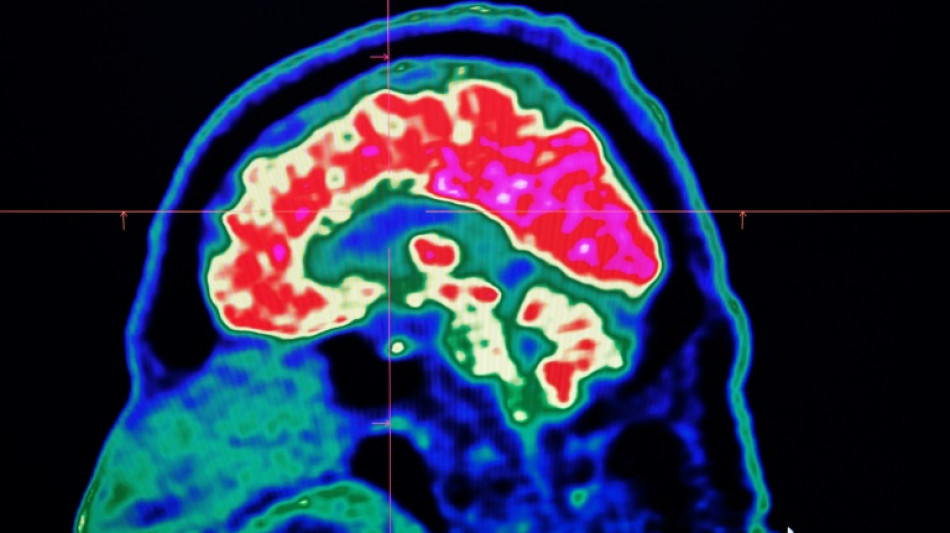

Surging nervous system disorders now top cause of illness: study / Photo: © AFP/File

Conditions affecting the nervous system -- such as strokes, migraines and dementia -- have surged past heart disease to become the leading cause of ill health worldwide, a major new analysis said on Friday.

More than 3.4 billion people -- 43 percent of the global population -- experienced a neurological condition in 2021, far more than had previously been thought, the analysis found.

Lead study author Jaimie Steinmetz of the IHME said the results showed that nervous system conditions are now "the world's leading cause of overall disease burden".

Cases of these conditions have soared by 59 percent in the last three decades, she said, with the increase mainly driven by the fact that the world's population was ageing and growing fast.

The researchers looked at how 37 different neurological conditions affected ill health, disability and premature death across 204 countries and territories from 1990 to 2021.

This data was used to estimate how many years of healthy life were lost to each condition, called disability-adjusted life years (DALYs).

More than 443 million years of healthy life were lost to nervous system disorders globally in 2021, an 18-percent increase from 1990, the study found.